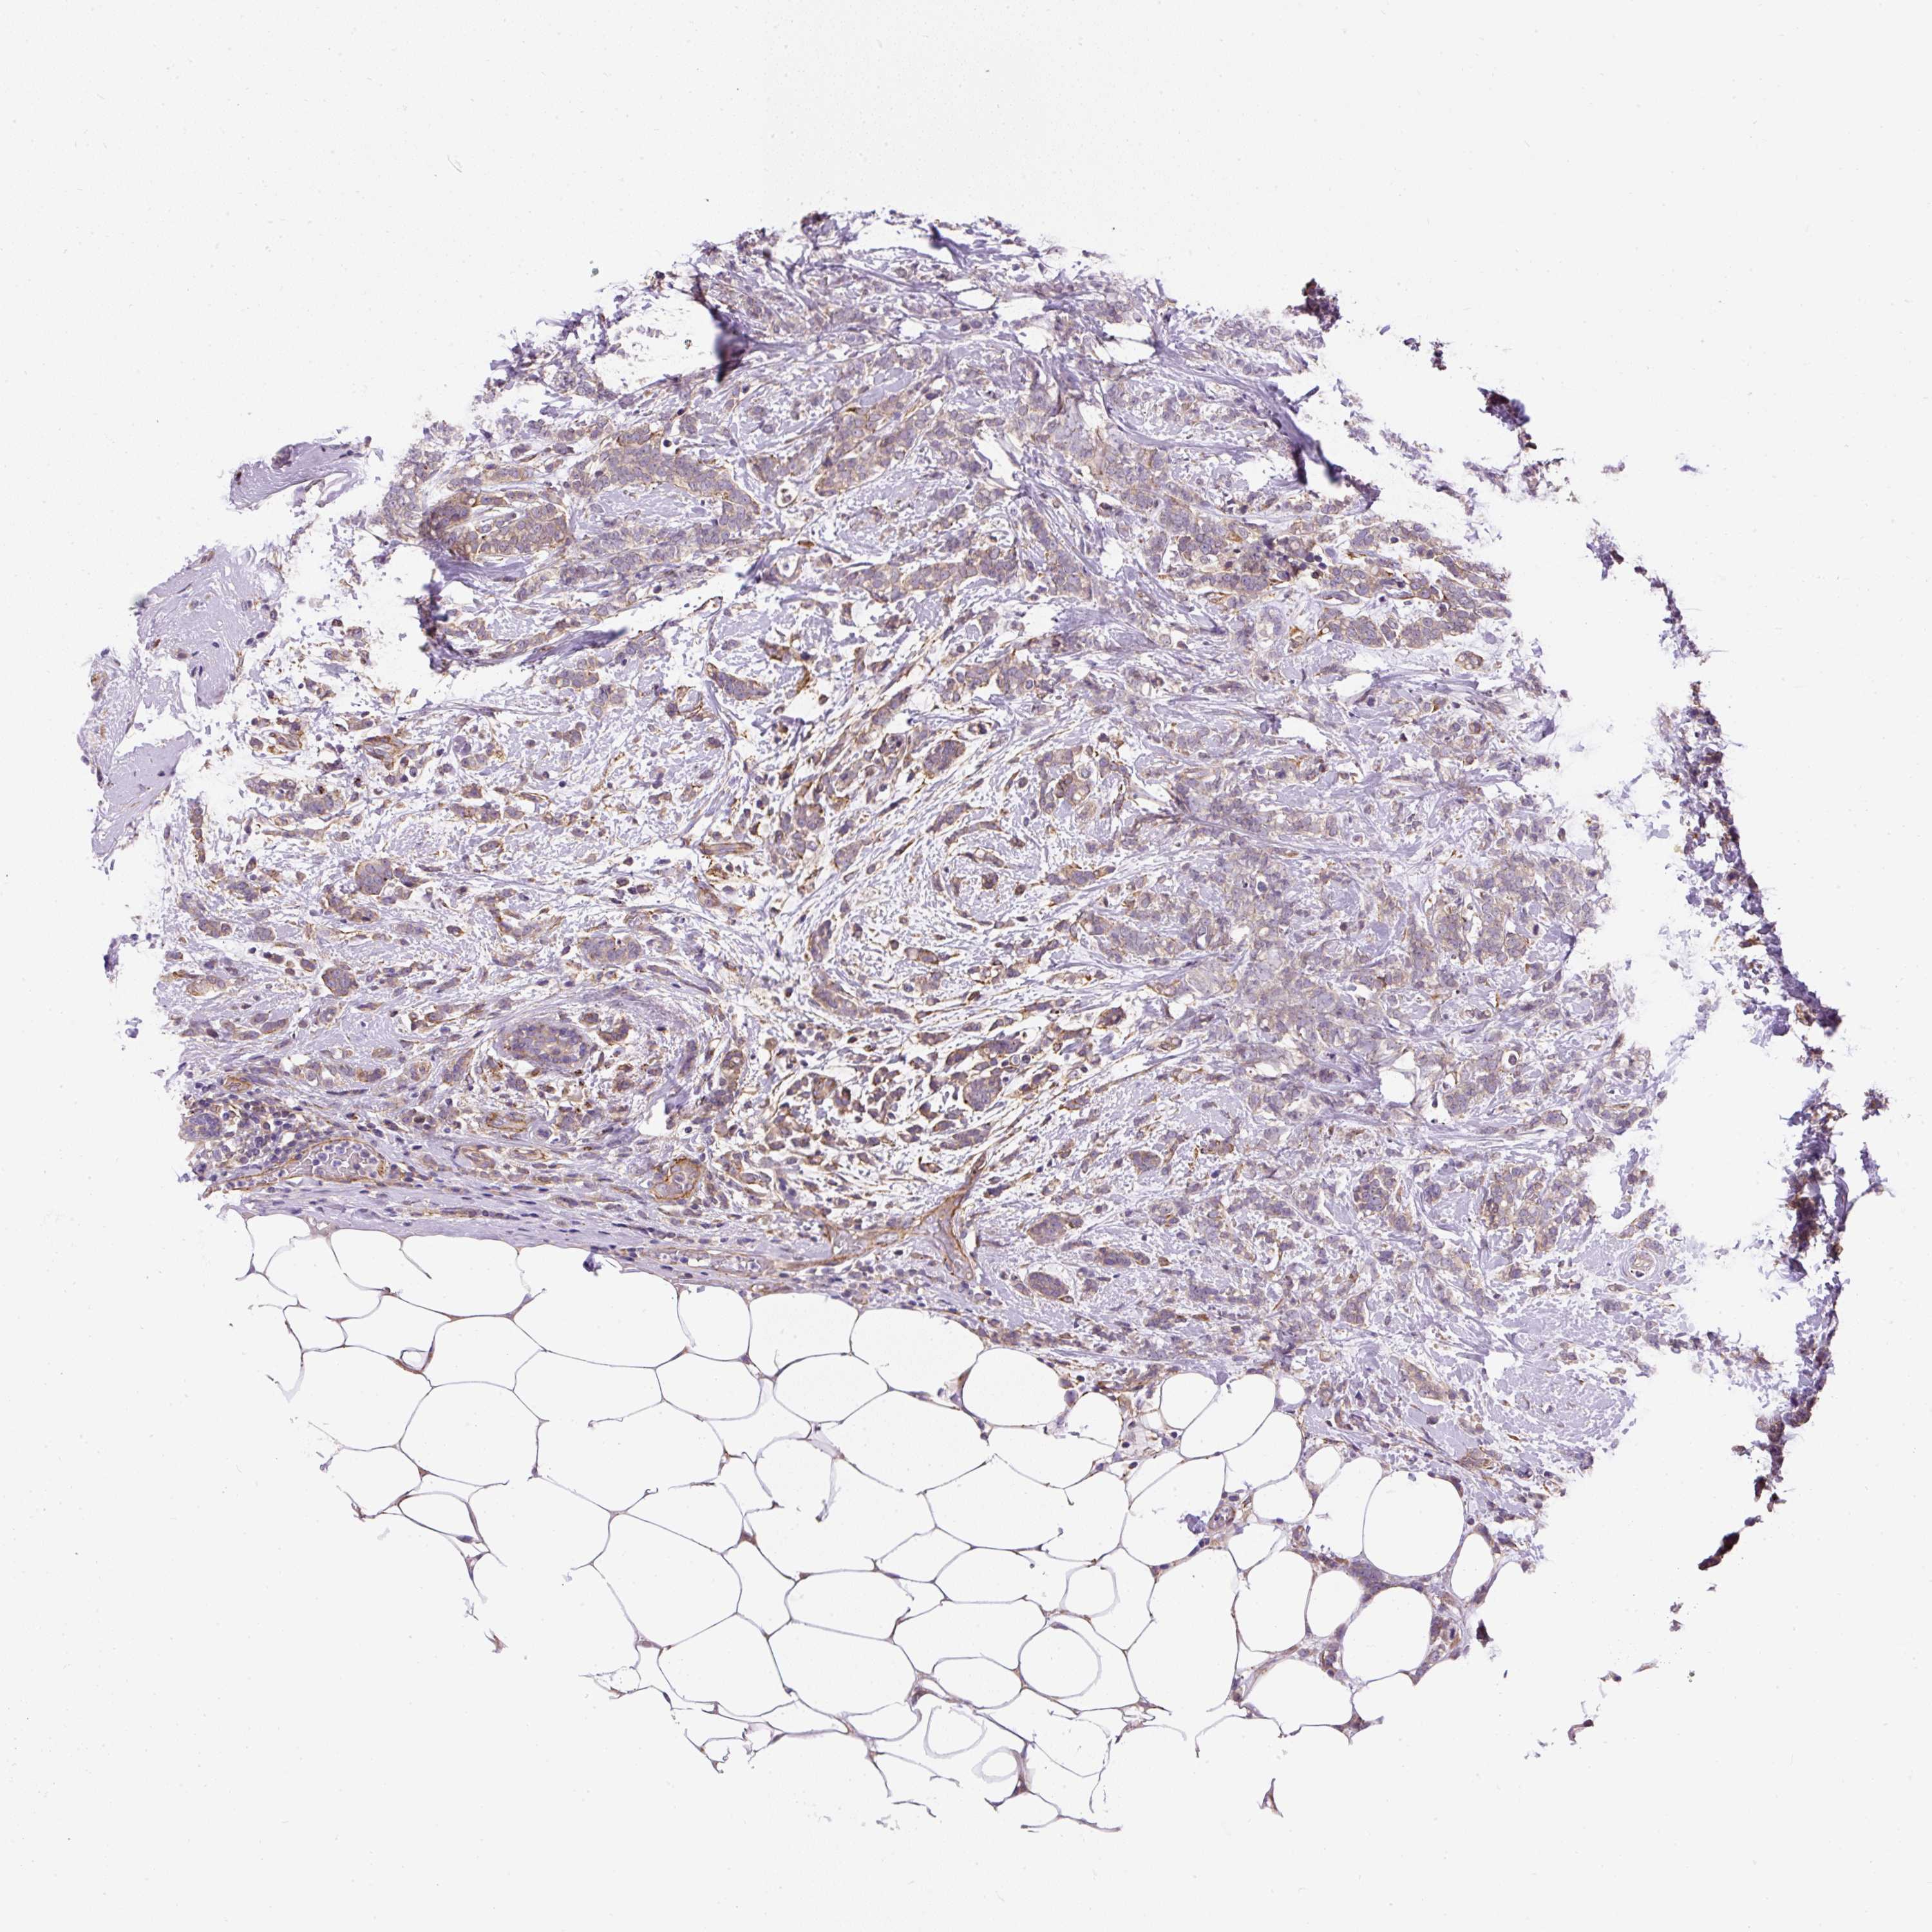

CANCER BREAST CANCER Show tissue menu

BRCA TCGA BRCA VALIDATION PROTEIN EXPRESSION